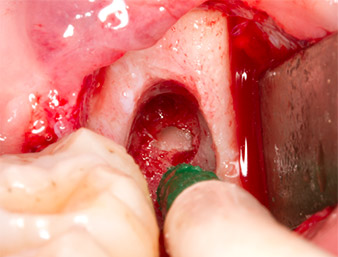

El tejido inflamatorio periapical se retiró también con sumo cuidado utilizando un excavador manual. La figura 12 muestra el alvéolo vacío con el nervio alveolar inferior expuesto.

A continuación, el tejido óseo autógeno (figura 13) se incorporó en el alvéolo y en el defecto óseo circundante (figura 14). Un velo de colágeno sirvió de protección para el nervio expuesto y cubrió las virutas óseas hasta el nivel del hueso (figura 15). Se aplicaron puntos de sutura con hilos Vicryl de grosor 4.0, que cerraron los tejidos blandos abiertos (figura 16). Tras la operación, se prescribió un preparado de ibuprofeno (Seractil 400 mg 3x1) y un antibiótico con amoxicilina y ácido clavulánico (Augmentine 1g 2x1).